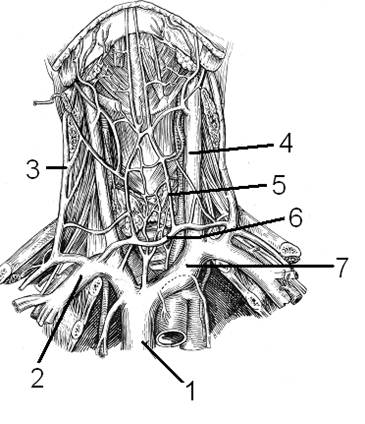

Анатомия внутренней яремной вены: КТ изображения